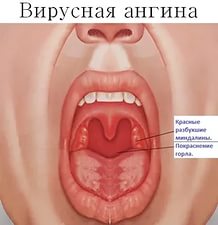

Первым признаком проявления заболевания является повышенная температура тела, ощущение общей слабости, чувство «ломоты». Буквально за несколько часов температура может подскочить до тридцати девяти градусов.

После этого начнется воспалительный процесс, и слизистая в полости рта покрывается сытью и через непродолжительное время появляются пузырьки (аналог герпеса на губах). Через несколько дней они самостоятельно начинают лопаться и превращаются в очень болезненные ранки. Из-за сильных болевых ощущений прием пищи сильно затруднен. Внешне ранки сильно напоминают гнойные язвочки.

На протяжении всего времени, у больного обильное слюноотделение, поскольку соответствующие рецепторы сильно раздражаются, боль при этом наблюдается настолько сильная, что больной не может глотать не только твердую пищу, но и пить напитки (чай) если температура его выше сорока градусов.